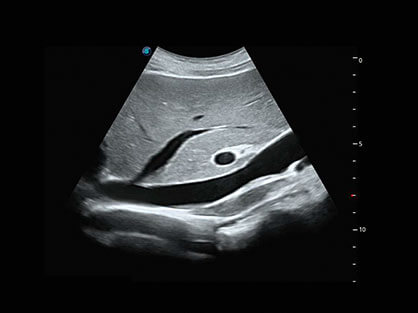

• AVC Follice卵泡自动测量

卵泡结构的自动识别和测量,可显示多组测量数据。

临床图